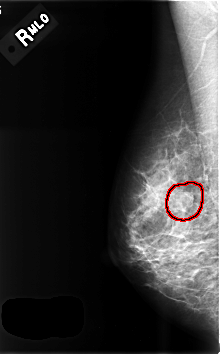

FILE: C_0507_1.RIGHT_MLO.OVERLAY

TOTAL_ABNORMALITIES 1

ABNORMALITY 1

LESION_TYPE MASS SHAPE ROUND MARGINS CIRCUMSCRIBED

ASSESSMENT 3

SUBTLETY 3

PATHOLOGY BENIGN

TOTAL_OUTLINES 1

BOUNDARY